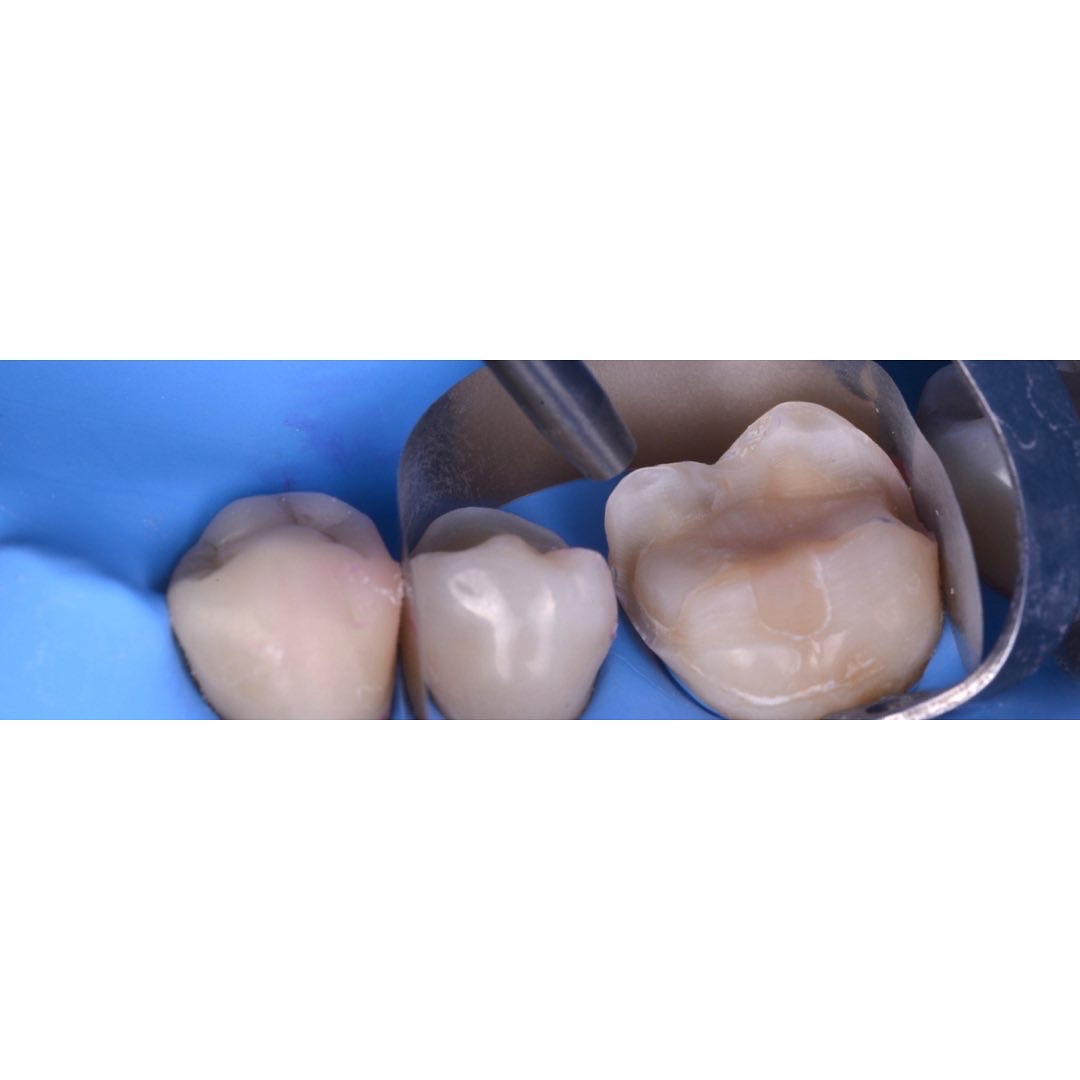

治療後